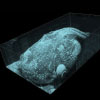

Click to Enlarge

Figure 116W Speckle variance measurement showing blood vessels of a mouse brain.

Speckle Variance Mode

The speckle variance imaging mode is an acquisition mode which uses the variance of speckle noise to calculate angiographic images. It can be used to visualize three dimensional vessel trees without requiring significant blood flow and without requiring a specific acquisition speed window. The speckle variance data can be overlaid on top of intensity pictures providing morphological information. Different color maps can be used to display the multimodal pictures.